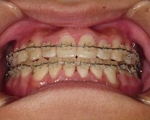

CASE3

前歯1本だけが出ています、矯正で治りますか?

(23歳/女性)↓

概要・担当医コメント:

前歯の唇側傾斜/マルチブラケット装置/非抜歯

動的治療期間15ヶ月(15回)/費用概算:60万円.

歯列アーチの形態修正に必要なスペースを微量のエナメル質の研磨により創生し,当初の計画通りに歯を移動させました.